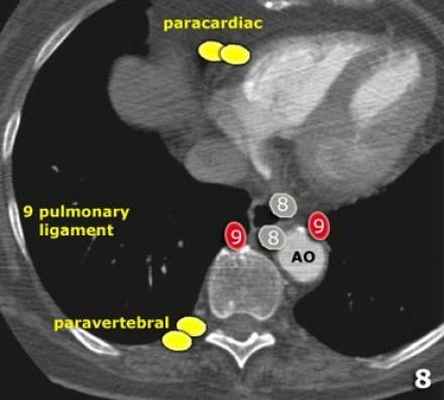

Нижние медиастинальные лимфатические узлы 7-9

7. Подкаринальные лимфатические узлы.

8. Параэзофагеальные лимфатические узлы. Лимфатические узлы ниже уровня карины.

9. Узлы легочной связки. Лежат в пределах легочной связки.

7. Подкаринальные лимфатические узлы

Эти лимфатические узлы расположены ниже уровня бифуркации трахеи (карины), но не относятся к нижнедолевым бронху и артерии. Справа они располагаются каудальнее нижней стенки промежуточного бронха. Слева они располагаются каудальнее верхней стенки нижнедолевого бронха.

Слева лимфатический узел 7 группы справа от пищевода.

8. Параэзофагеальные лимфатические узлы

Эти лимфатические узлы ниже подкаринальных лимфатических узлов и распространяются каудальнее до диафрагмы.

На изображении слева ниже уровня карины справа от пищевода обозначен лимфатический узел 8 группы.

9. лимфатические узлы легочной связки

Данные лимфатические узлы лежат в пределах легочной связки, в том числе и по ходу нижней легочной вены. Легочная связка представлена дупликатурой медиастинальной плевры охватывающей корень легкого.